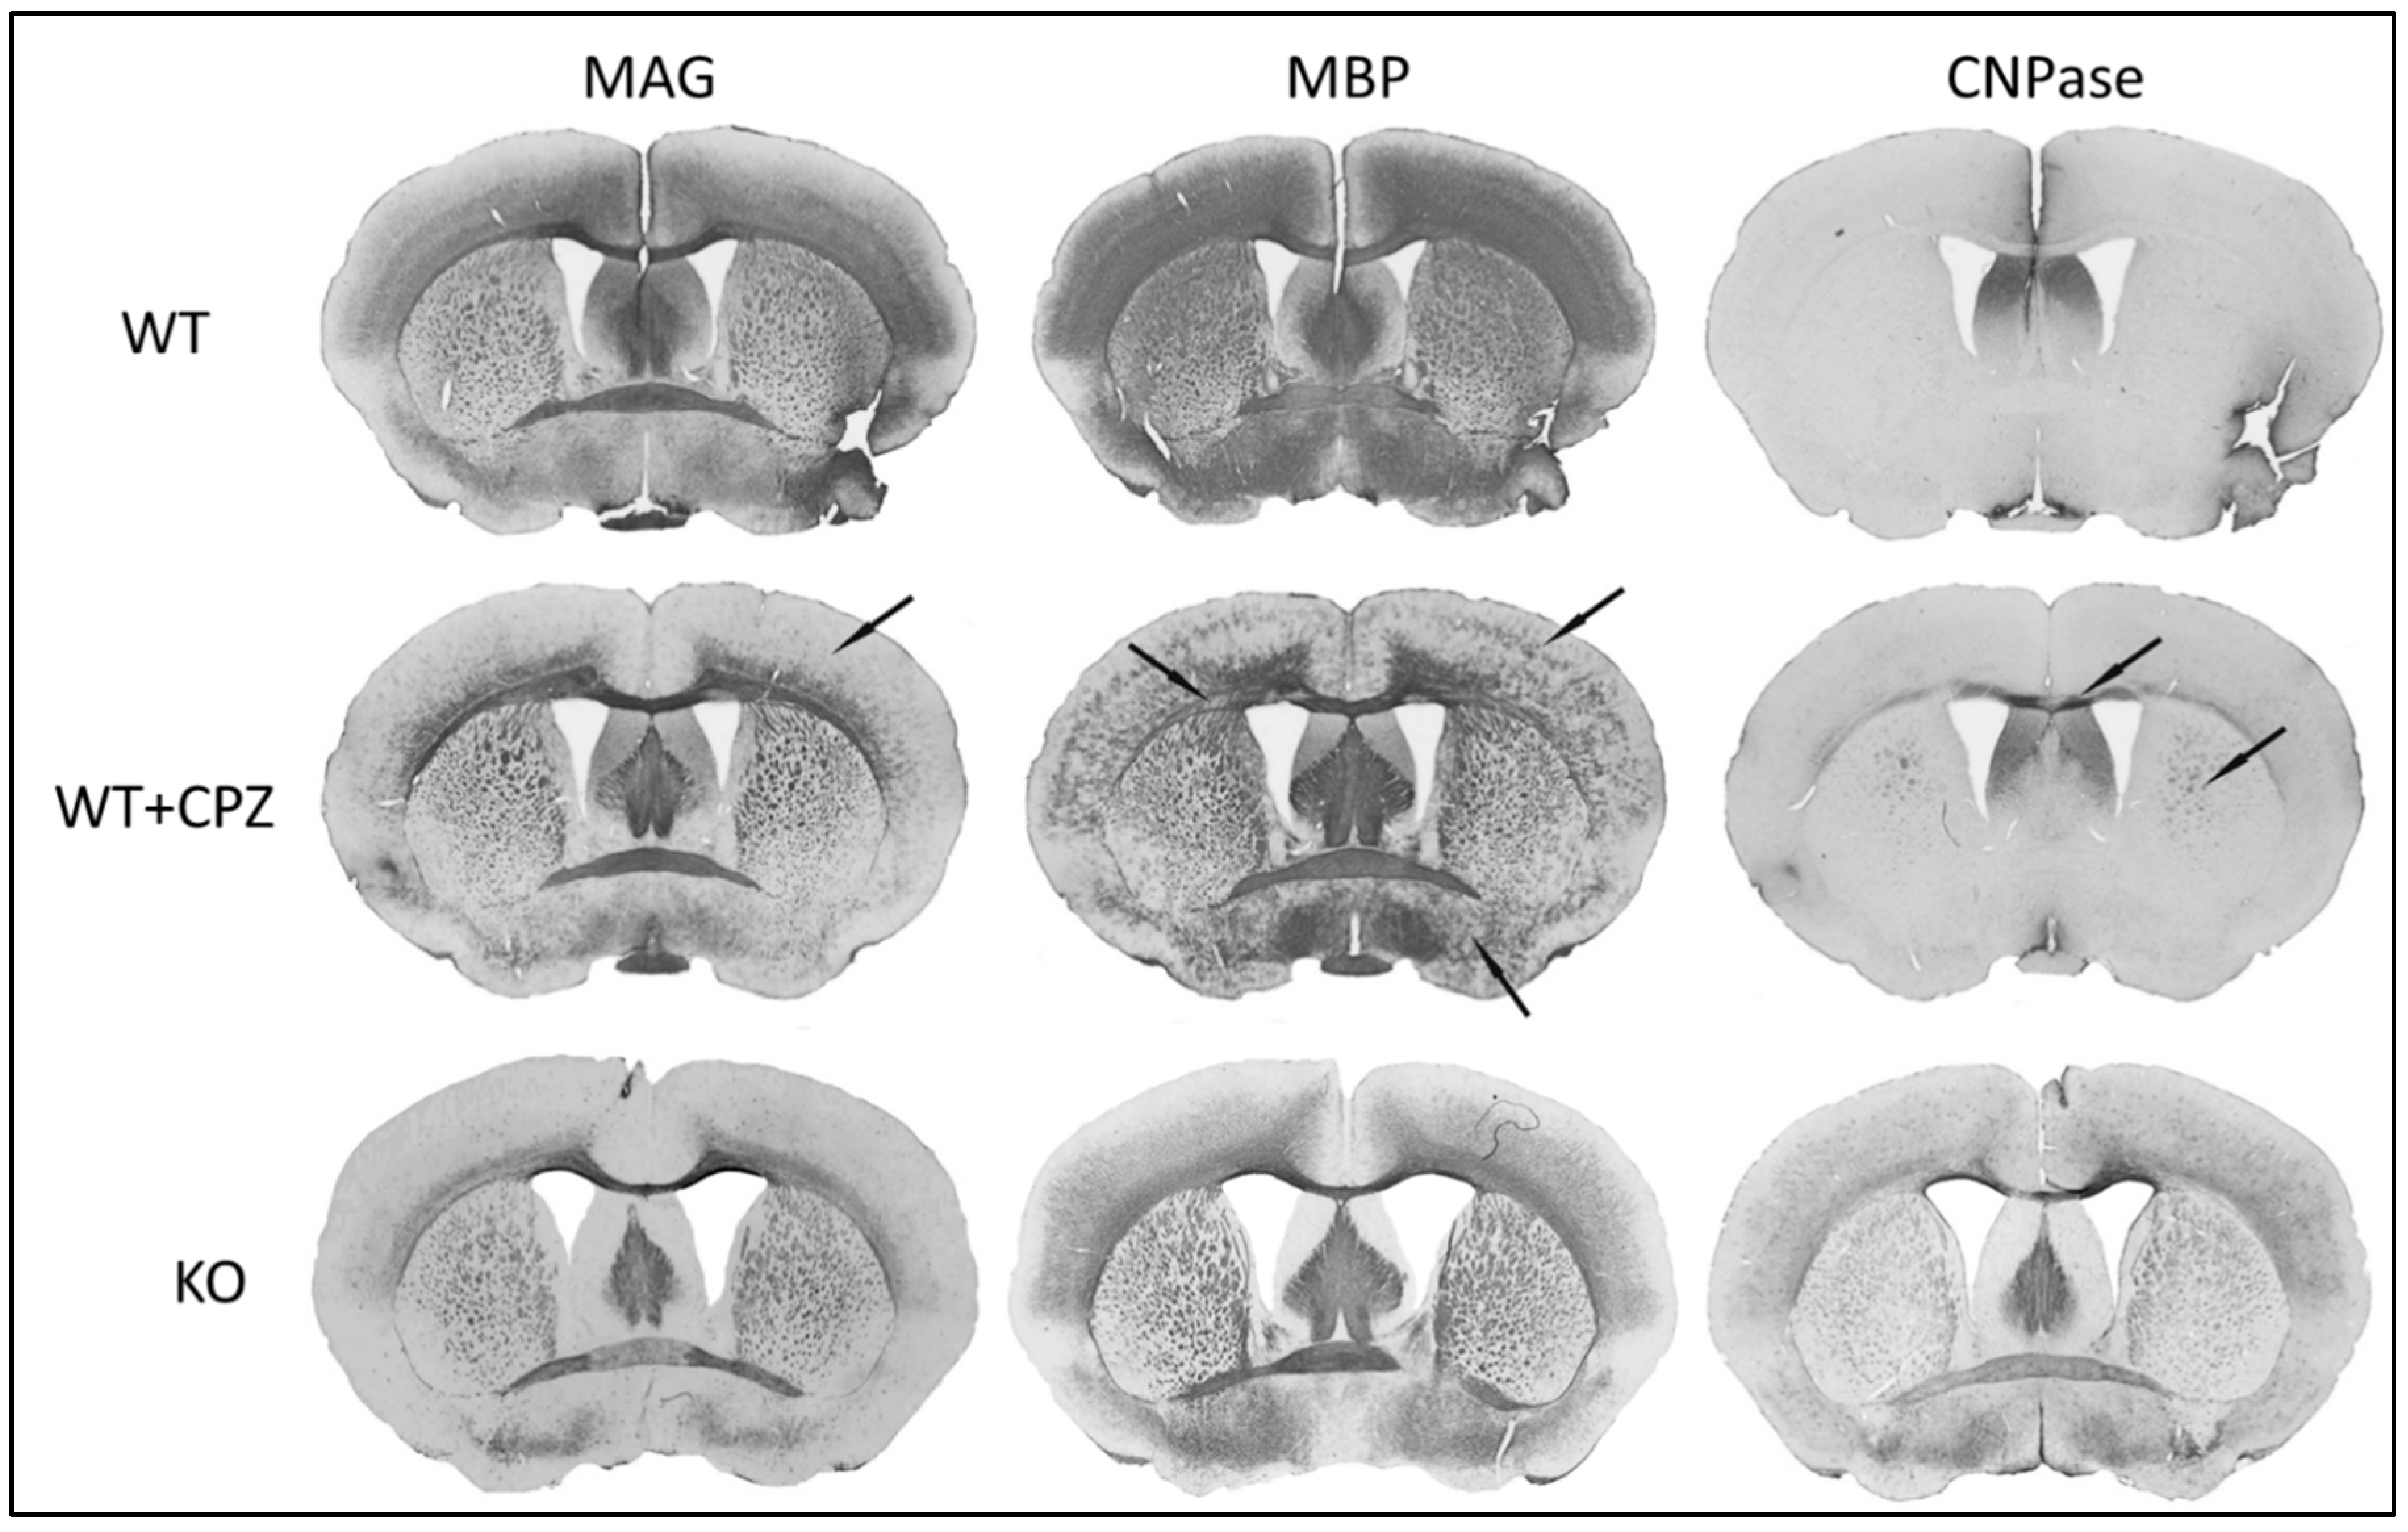

3.5. Immunohistochemistry

To assess the efficacy of cuprizone treatment in wild-type mice, we used myelin markers (anti-MAG, anti-MBP and anti-CNPase antibodies) to compare WT mice with WT + CPZ animals and with KO animals. Coronal sections of the forebrain at the level of the anterior commissure are shown in Figure 4. All three antibodies used—anti-MAG, anti-MBP and anti-CNPase—recognize epitopes on oligodendrocytes.

Figure 4 shows that KO mice have the lowest MAG levels. WT + CPZ mice also show a loss of MAG protein expression, particularly in the middle layers of the cortex and, to a lesser extent, in large fiber bundles such as the corpus callosum and anterior commissure. Dramatic changes can be observed in the expression of the MBP protein. The CNPase protein is only weakly expressed in the brains of WT mice, but its expression increases in WT + CPZ mice, especially in the large bundles of commissural fibers in the corpus callosum, the main migration pathway for adult oligodendrocyte progenitor cells. The phenomenon of increased CNPase expression is particularly pronounced in the brains of KO mice, where it is observed in all layers of the cortex and commissures.

To further analyze the corpus callosum, we quantified the immunohistochemical staining of the myelin markers MAG, MBP and CNPase. As shown in Figure 5, our results indicate that MAG expression increases in WT + CPZ mice (p < 0.01) compared with WT mice, while it decreases in KO mice (p < 0.01). MBP expression changes from homogeneous staining in WT animals to a focal loss of staining in WT + CPZ animals, but its overall expression is increased (p < 0.01). MBP is not strongly altered in KO mice. CNPase showed the greatest change—its reactivity increased throughout the commissural bundle in both WT + CPZ (p < 0.01) and KO (p < 0.01) compared with WT mice, in which CNPase expression is very low.

Figure 4. Immunohistochemical staining of myelination markers (MAG, MBP and CNPase) in the brains of wild-type (WT), cuprizone-treated wild-type (WT + CPZ) and B4galnt1-null (KO) mice on coronal sections of the forebrain. The arrows indicate the sites with the greatest differences in the distribution of the individual markers.

To achieve comparable demyelination to that in B4galnt1-null mice, WT mice were treated with cuprizone, which effectively mirrors demyelination, including loss of the myelin proteins MBP and MAG. Demyelination does not affect all brain regions equally in the two mouse models studied, which could also explain the differences in the effects of the two anesthetics. Studies in rat models suggest that demyelination is more pronounced in the cerebral cortex than in the subcortical white matter, which we also confirmed with anti-MAG and anti-MBP antibodies. Interestingly, the large fiber bundles in the brainstem show no significant changes in myelin protein [18,21]. Our results showed that B4galnt1-null mice have the lowest MAG levels, which is consistent with previous findings [35]. Cuprizone-treated mice exhibited a marked loss of MAG expression, particularly in the middle layers of the cortex and, to a lesser extent, in large fiber bundles such as the corpus callosum and anterior commissure. Cuprizone induces demyelination by targeting oligodendrocytes, leading to their apoptosis and the subsequent loss of myelin proteins, including MAG. The pattern of MAG reduction suggests that cuprizone treatment disrupts the myelin sheath and particularly affects regions with high myelin turnover or regenerative requirements [18,19]. Quantification revealed an increase in MAG expression in cuprizone-treated mice compared with WT mice, which may indicate a compensatory response to the initial myelin damage that aims to stabilize and repair myelin sheaths. This adaptive response could be an attempt by the surviving oligodendrocytes to promote myelin regeneration and maintain axonal integrity. Another explanation is that the initial demyelination in these structures has led to increased access/availability of these proteins to antibodies. This hypothesis is supported by the presence of GD1a and GT1b in the same fibers. Functional studies have shown that these two gangliosides are receptors for MAG [36], which was questionable as there was no reactivity immunohistochemically to monoclonal antibodies directed against GD1a and GT1b in the large fiber bundles in wild-type mice. The presence of these gangliosides on fibers affected by demyelination may therefore be evidence that these epitopes exist and are accessible to highly specific monoclonal antibodies directed against them. We have also observed similar results with MBP. Our results show that the WT animals exhibited homogeneous MBP staining, while the cuprizone-treated animals showed focal MBP staining, indicating areas of myelin loss, but with an overall increase in MBP expression. This supports the assumption that demyelination only increased access for antibodies and did not decrease the expression of this epitope. The focal staining suggests localized demyelination caused by cuprizone treatment, which is known to induce apoptosis of oligodendrocytes and patchy demyelination [18]. Despite the localized losses, the overall increase in MBP expression could be attributed to compensatory upregulation in response to the initial myelin damage, representing an attempt by surviving oligodendrocytes to enhance remyelination and restore myelin integrity [19]. The unchanged MBP levels in B4galnt1-null mice underscore the chronic nature of their demyelination and reflect a different pathophysiology [16].